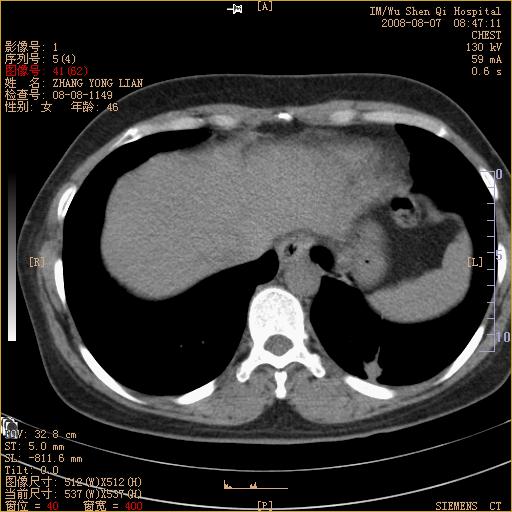

标题: CT15050:女,46岁,咳嗽胸痛一月余 [打印本页]

脾脏低密度结节转移不排除。

1)考虑左肺下叶后基底段周围型肺癌伴纵隔淋巴结转移。2)脾内低密度灶,性质待定;不排除转移瘤可能。